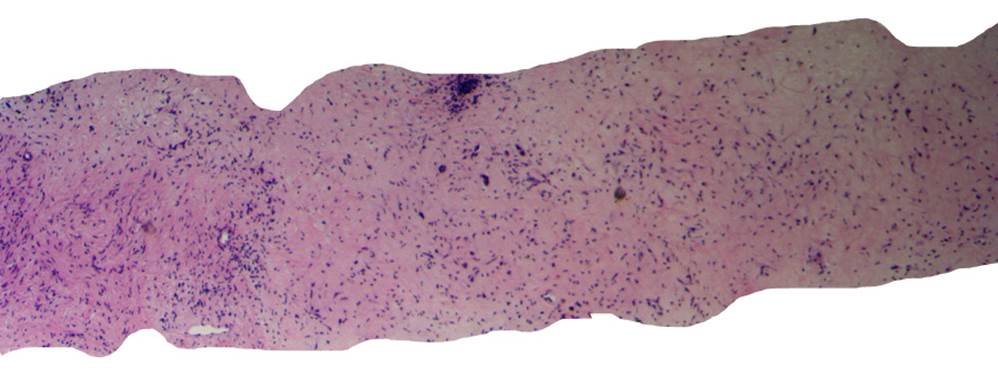

| Figure 1: 4x, 1st biopsy core. |

| Figure 2: 10x, 1st biopsy core. |

Its histologic features are quite distinctive in the liver. In hepatic EHE the tumor is often multifocal, with calcifications seen radiographically. They are firm, white to yellow, with ill-defined borders. Tumor cells are both dendritic and epithelioid in various proportions. The spindle cells are irregularly shaped and elongated. Epithelioid cells are rounder with more abundant eosinophilic cytoplasm. Small papillations or tufts of tumor cells may be seen within thin-walled vascular spaces. Abortive vascular differentiation is typically seen, with tumor cell cytoplasm containing a single vacuole representing a capillary luminal space — so-called “blister cells.” Tumor cells lie within a variably myxoid to fibrous stroma. The tumor often infiltrates hepatic vein and portal vein branches, leading to Budd-Chiari syndrome as a possible presentation. The tumor tends to grow around and leave pre-existing hepatic structures intact, particularly at the periphery of tumor nodules. In these areas, only subtle infiltration of tumor cells may be seen within sinusoids, in an otherwise architecturally normal liver, something which can be particularly treacherous in small liver biopsies.

In the second setting, the tumor is hypocellular and has a fibrotic stroma, and can closely mimic fibrosis or confluent necrosis with drop-out. In this setting, the tumor can be very difficult to diagnose on limited core biopsy material. One can look for focal areas of greater cytologic atypia, or areas of sinusoidal infiltration of tumor cells. A vascular IHC stain can be helpful to highlight such infiltration, keeping in mind not to misinterpret capillarization of sinusoids, which can be seen in various settings.